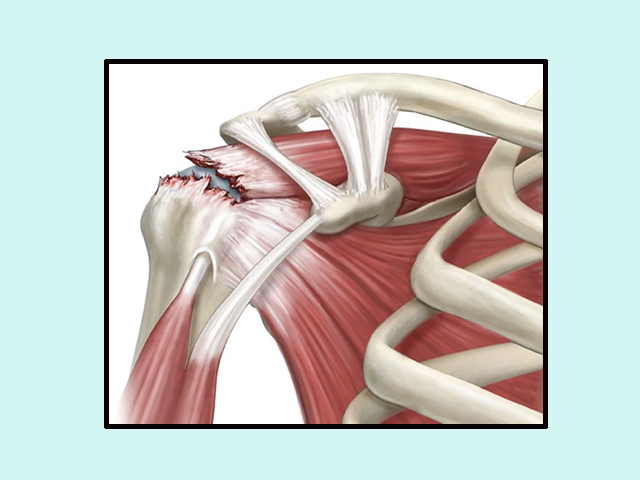

MOST COMMON INJURY IN ELDERLY IS CUFF TEAR WHICH IS AGE RELATED MOST OF THE TIMES. THIS REQUIRES REPAIR FOR NORMAL FUNCTIONING OF SHOULDER.